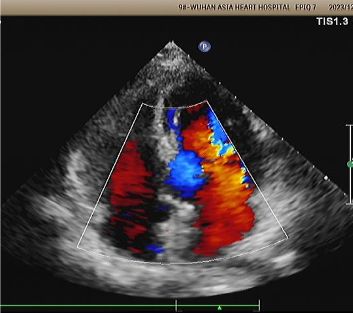

Écho d'une année:

No visible disc structures – replaced by 8mm tissue thickening at the septal implant site.

Zero residual shunt (rest or post-Valsalva).

Absorption complète de l'appareil confirmée.